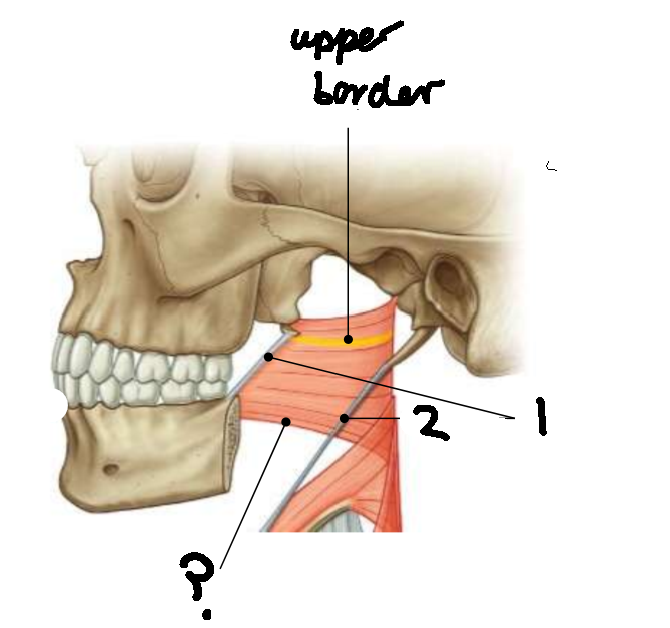

What muscle is this?

superior constrictor

What is the upper border of this muscle?

palatopharyngeal sphincter

What is 1?

pterygomandibular raphe

What is 2?

stylohyoid ligament

What are the attachments of this muscle?

pterygoid hamulus, pterygomandibular raphe, posterior end of mylohyoid line → pharyngeal raphe